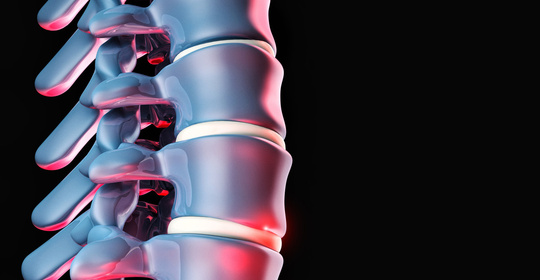

脊椎頭痛的診斷、治療與預防